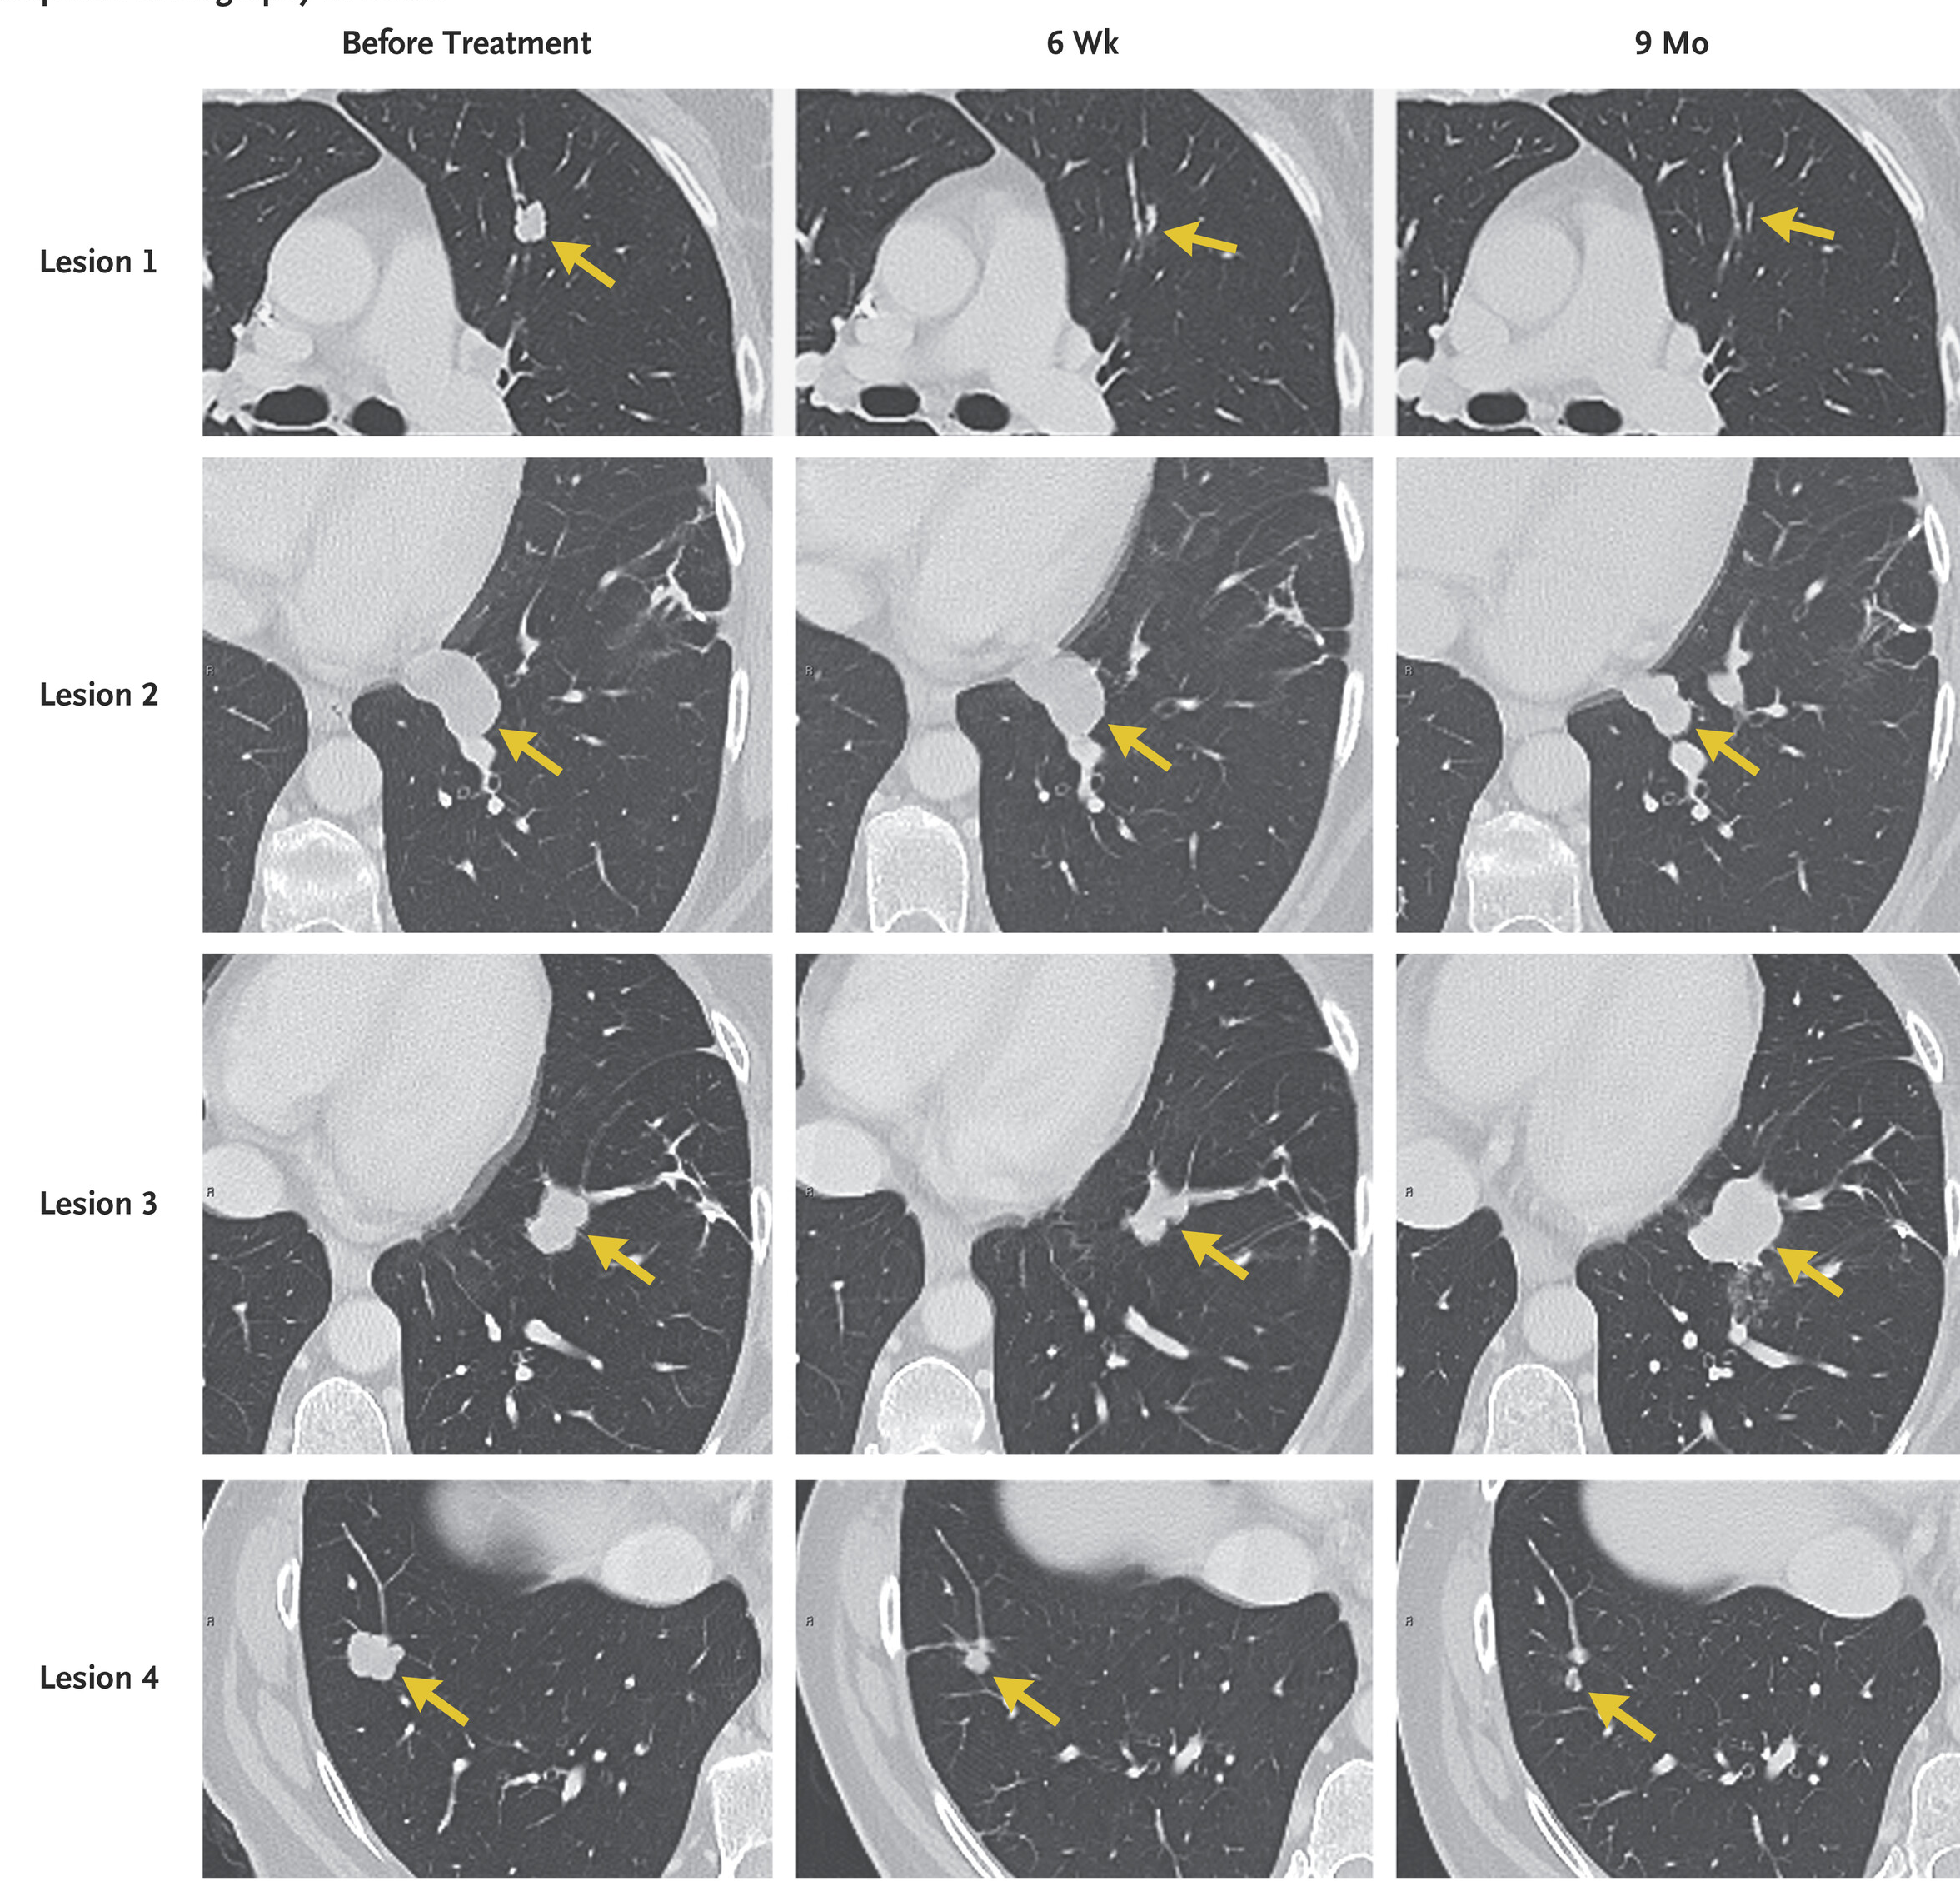

近日,《Neuro-Oncology》在线全文发表了埃克替尼联合阿美替尼一线治疗EGFR突变伴脑转移非小细胞肺癌患者的疗效与安全性的一项I/II期临床研究的研究结果。